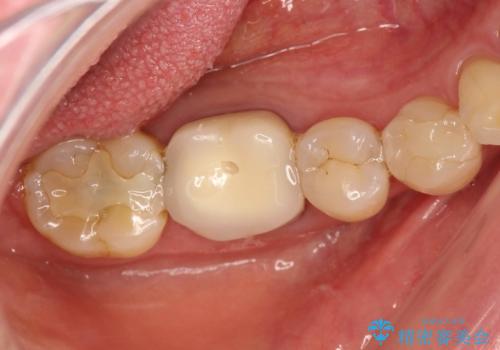

[深い虫歯] 根管治療・歯周外科治療を行い歯を保存する

![[深い虫歯] 根管治療・歯周外科治療を行い歯を保存するの症例 治療前](https://seimitsushinbi.jp/wp/wp-content/uploads/2019/10/565cd81632432c46200480d3f4728f8d-500x350.jpg?v=1572444569)